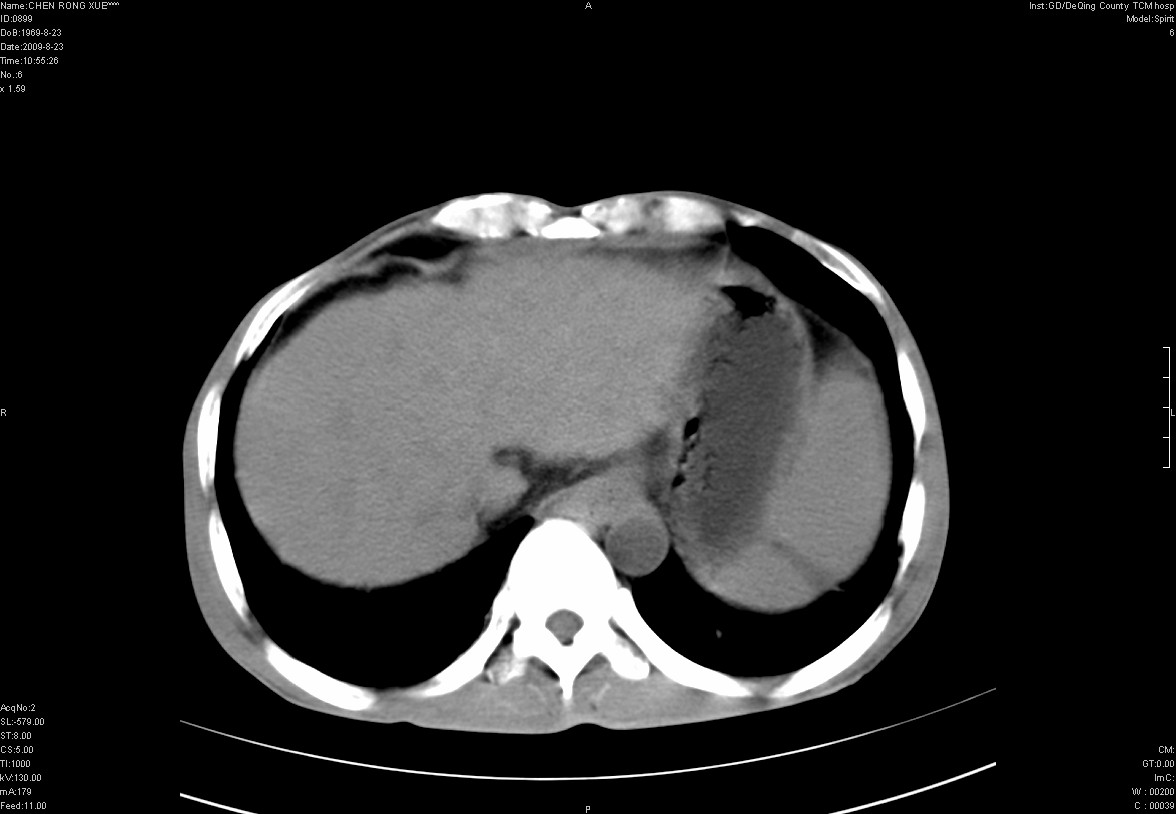

以下是引用zxl51642在2009-8-23 12:56:00的发言:[br]1、肝硬化、脾大;2、慢性胆囊炎;3、右肾占位并右侧腰大肌受侵,考虑恶性可能性大,建议增强扫描进一步检查。

以下是引用qiuleiyu在2009-8-23 15:17:00的发言:[br]1、慢性肝病,肝硬化,脾大,门脉高压。胆囊小结石。[br]2、右肾明显肿大,伴片状低密度灶,累及右侧腰大肌,肿瘤及炎症性病变皆有可能大,建议增强。

以下是引用zjzjr在2009-8-23 17:42:00的发言:[br]1、慢性肝病,肝硬化,脾大,门脉高压。胆囊小结石。[br]右肾脓肿波及肾周,建议增强